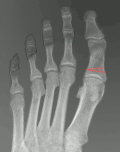

Hallux valgus (před operací) -

Hallux valgus (po operaci) -

Hallux valgus (rtg. kombinace lečení) -